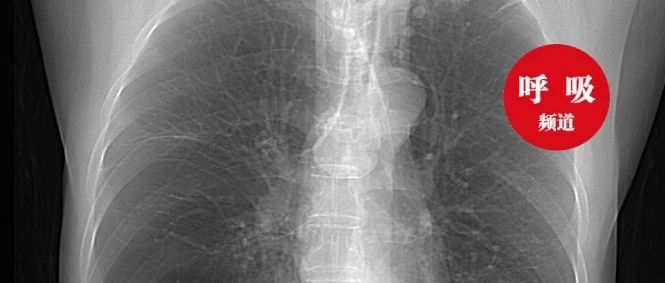

间质性肺炎的典型图谱,最全解析!

*仅供医学专业人士阅读参考经典的间质性肺炎,就是一张网!  有网友留言,谈谈间质性肺炎。那就先说说间质性肺炎的经典改变。网格 ≈ 间质性肺炎间质性肺炎的影像学表现,复杂的很复杂,有时候和肺炎不容易区分。经典的间质性肺炎,就是一张网!图1-2经典的间质性肺炎的特点:1.胸膜下2.网格状图3-4很多间质性肺炎,都有这个特征,是间质性肺炎的入门知识,也是很重要的知识。假如一个患者患有结缔组织病,双肺多发病变,但是胸膜下没有病灶,首先不考虑间质性肺炎,要考虑其他疾病。...